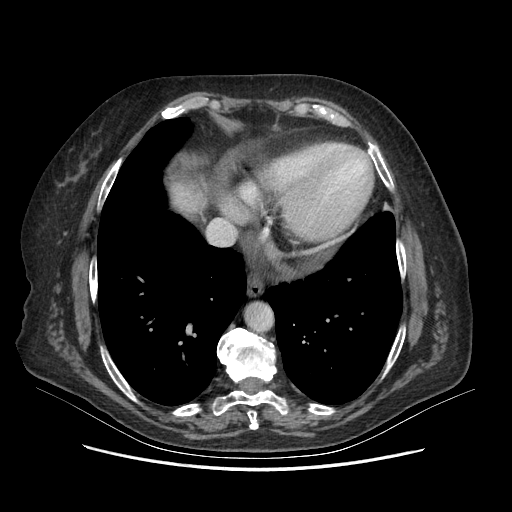

Generated VENOUS CT scan (A→B translation)

No window - Raw intensity values